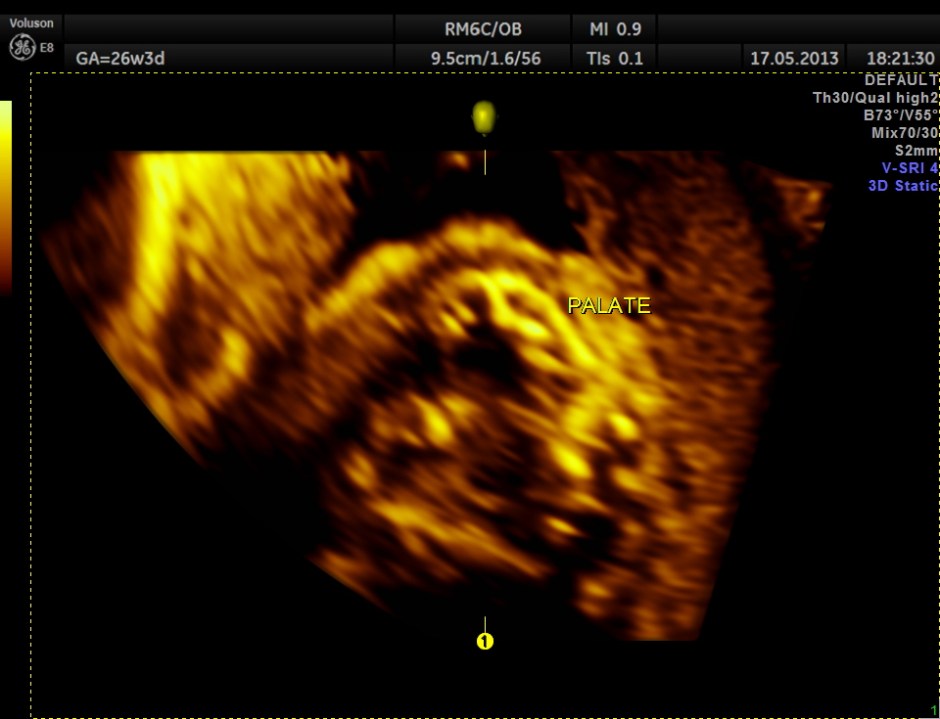

The following images show the face and the palate.

This fetus did not show any oro-facial clefts ; heart and spine appeared normal.